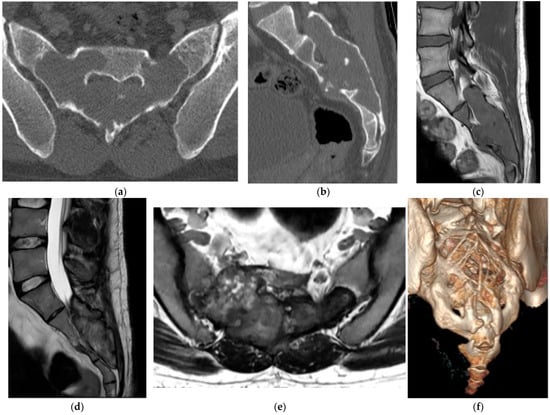

2.5.2. Aneurysmal Bone Cyst

- Restrepo, R.; Zahrah, D.; Pelaez, L.; Temple, H.T.; Murakami, J.W. Update on Aneurysmal Bone Cyst: Pathophysiology, Histology, Imaging, and Treatment. Pediatr. Radiol. 2022, 52, 1601–1614. [Google Scholar] [CrossRef]

- Palmisciano, P.; Hunter, M.; Lokesh, N.; Bin Alamer, O.; Scalia, G.; Giammalva, G.R.; Maugeri, R.; Iacopino, D.G.; Umana, G.E.; Haider, A.S. Aneurysmal Bone Cyst of the Spine in Adult Patients: A Systematic Review and Comparison of Primary vs Secondary Lesions. J. Clin. Neurosci. 2022, 100, 15–22. [Google Scholar] [CrossRef]

- Czervionke, L.F. Aneurysmal Bone Cyst. In Imaging in Spine Surgery, 1st ed.; Ross, J.S., Bendok, B.R., McClendon, J., Jr., Eds.; Elsevier: Amsterdam, The Netherlands, 2017; pp. 54–59. [Google Scholar]